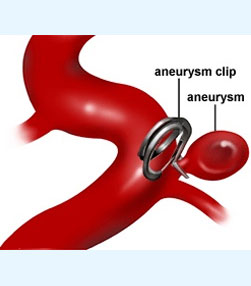

- Vascular neurosurgery - More than 500 aneurysms including 8 basilar top aneurysms, 40 arteriovenous malformations